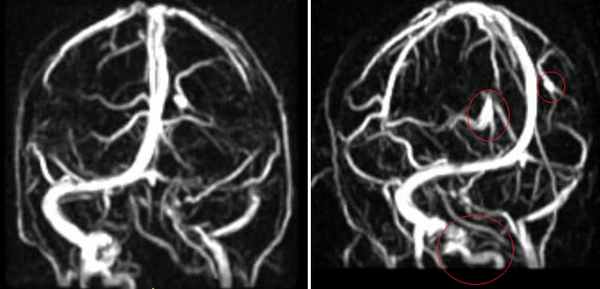

МРА-картина выраженной асимметрии венозной сети с преобладанием и нерезкой дилатацией вен правой гемисферы (поперечного, сигмовидного синусов и яремной вены справа); гипоплазии левого поперечного и сигмовидного синуса. Единичные участки (2) локального расширения вен в парасагиттальных отделах левой гемисферы, большой вены мозга. Асимметричная, расширенная и выражено извитая венозная структура экстракраниальных отделов справа.

МРА признаки незначительной дилатации верхнего сагиттального синуса, локального снижения кровотока и сужения просвета дистальных отделов прямого синуса; асимметрии просвета поперечных, сигмовидных синусов и внутренних яремных вен.